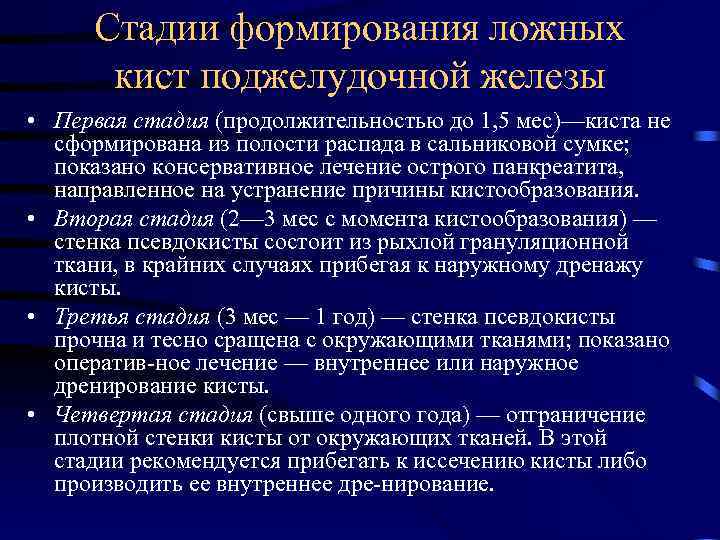

Стадии формирования ложных кист поджелудочной железы • Первая стадия (продолжительностью до 1, 5 мес)—киста не сформирована из полости распада в сальниковой сумке; показано консервативное лечение острого панкреатита, направленное на устранение причины кистообразования. • Вторая стадия (2— 3 мес с момента кистообразования) — стенка псевдокисты состоит из рыхлой грануляционной ткани, в крайних случаях прибегая к наружному дренажу кисты. • Третья стадия (3 мес — 1 год) — стенка псевдокисты прочна и тесно сращена с окружающими тканями; показано оператив ное лечение — внутреннее или наружное дренирование кисты. • Четвертая стадия (свыше одного года) — отграничение плотной стенки кисты от окружающих тканей. В этой стадии рекомендуется прибегать к иссечению кисты либо производить ее внутреннее дре нирование.